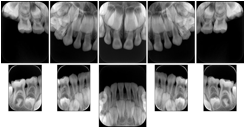

- OO-1. Intra-oral Full Mouth Series Structured Display